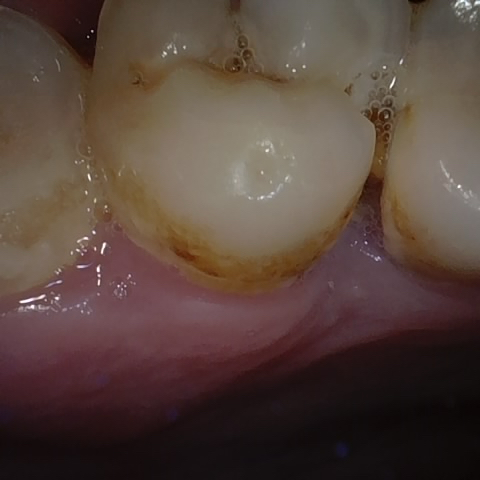

Annotated as "Good"